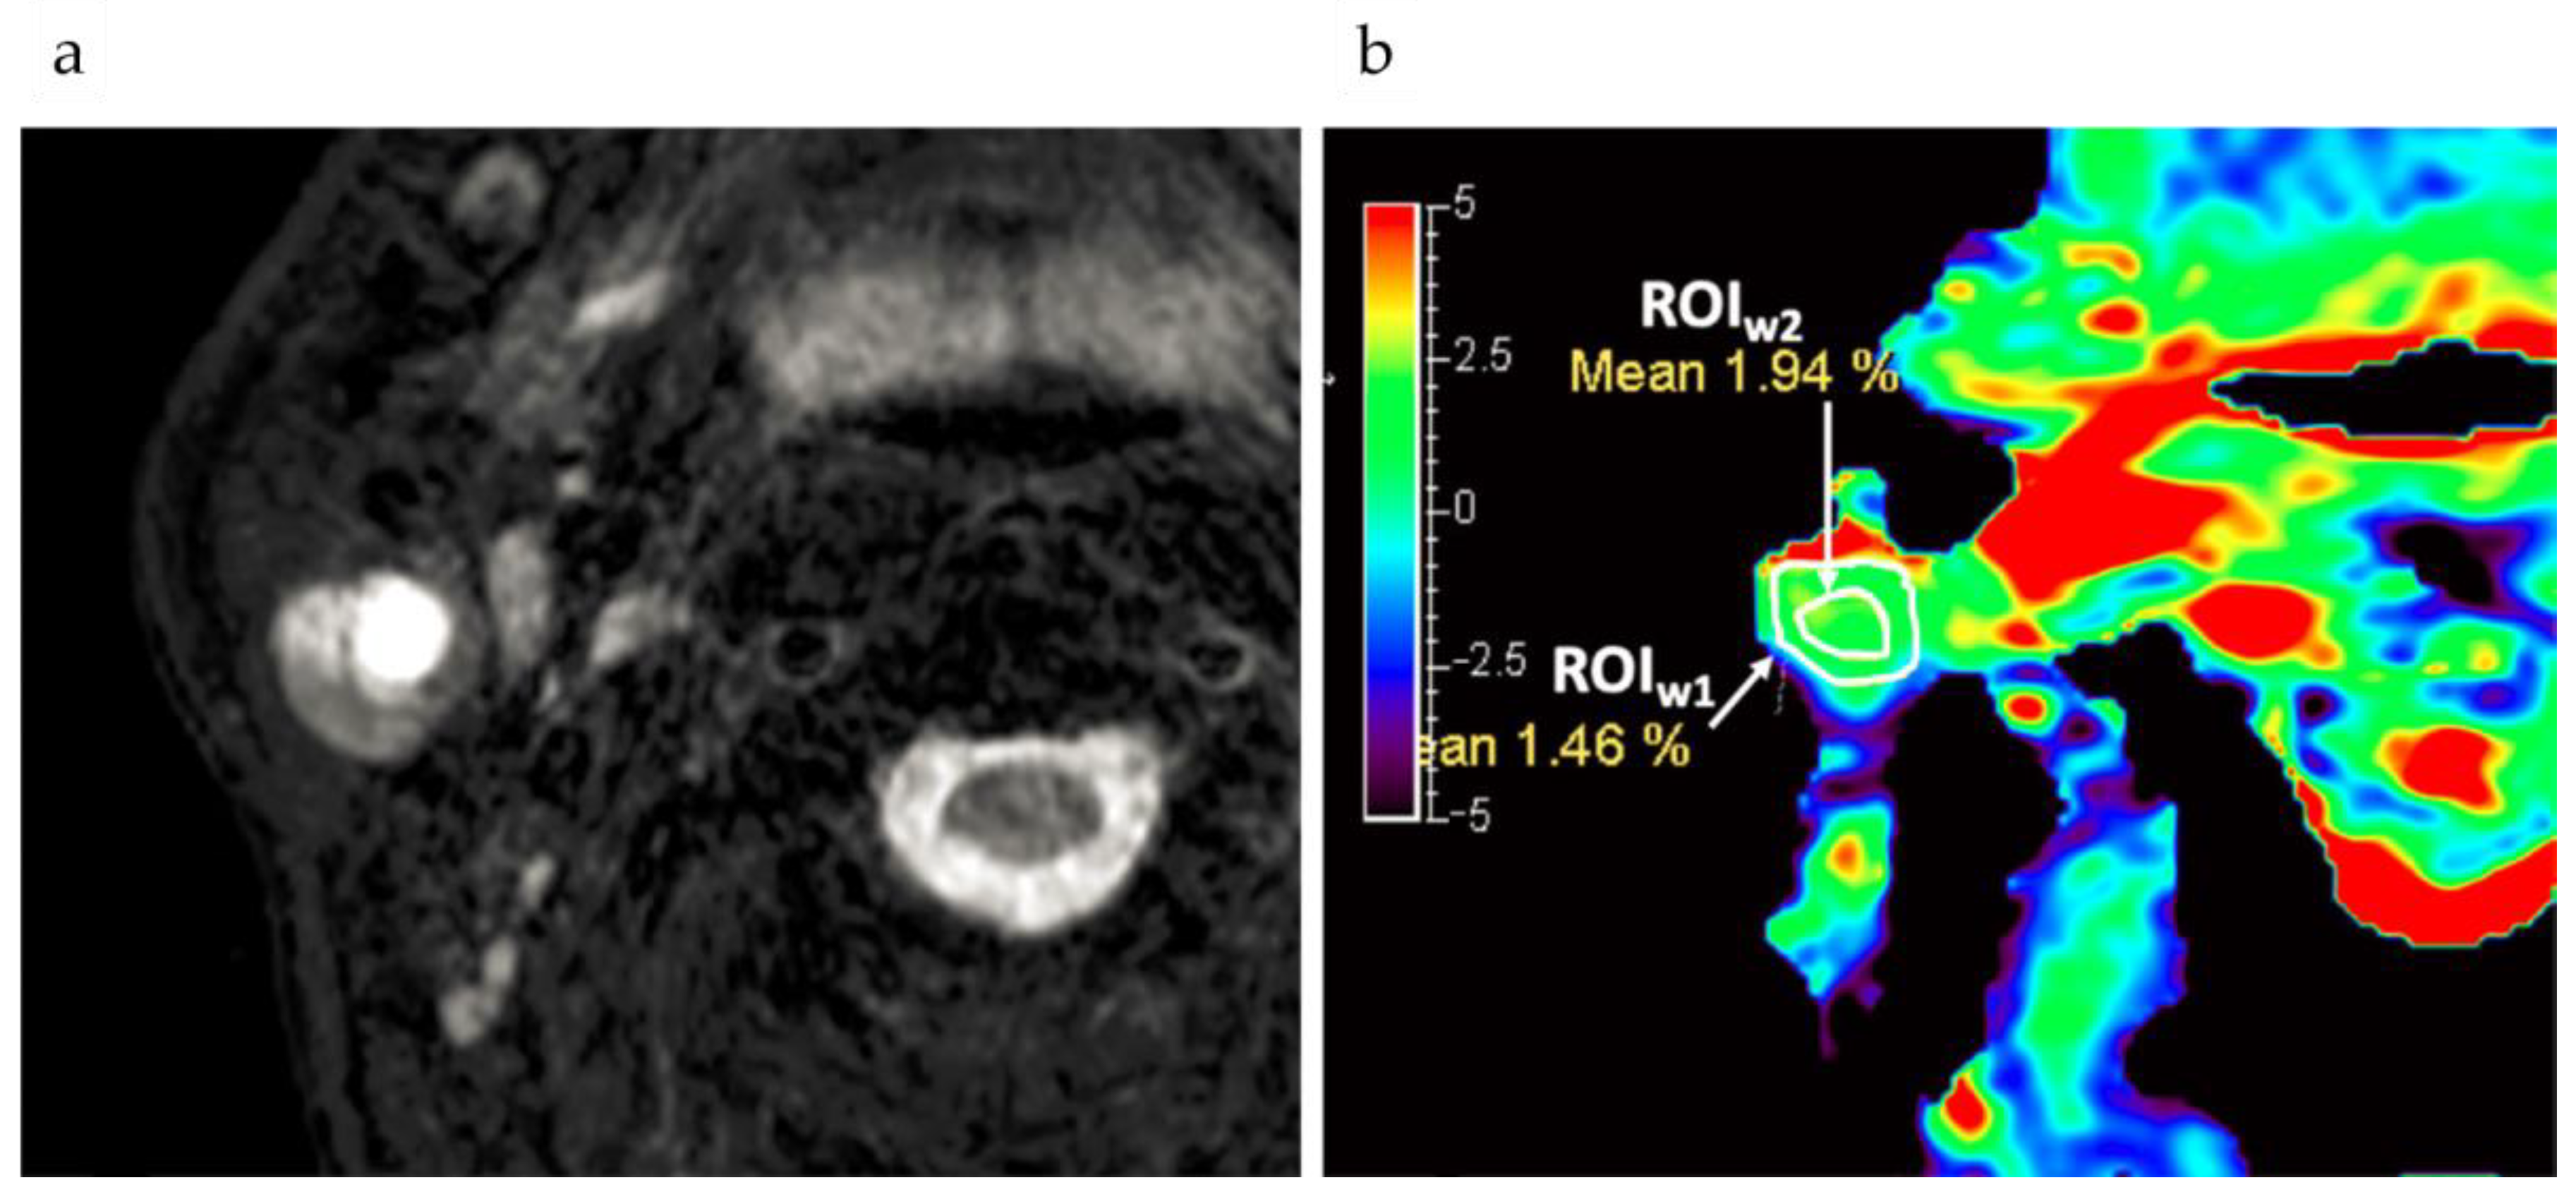

- Jones, K.M.; Randtke, E.A.; Yoshimaru, E.S.; Howison, C.M.; Chalasani, P.; Klein, R.R.; Chambers, S.K.; Kuo, P.H.; Pagel, M.D. Clinical Translation of Tumor Acidosis Measurements with AcidoCEST MRI. Mol. Imaging Biol. 2017, 19, 617–625. [Google Scholar] [CrossRef]